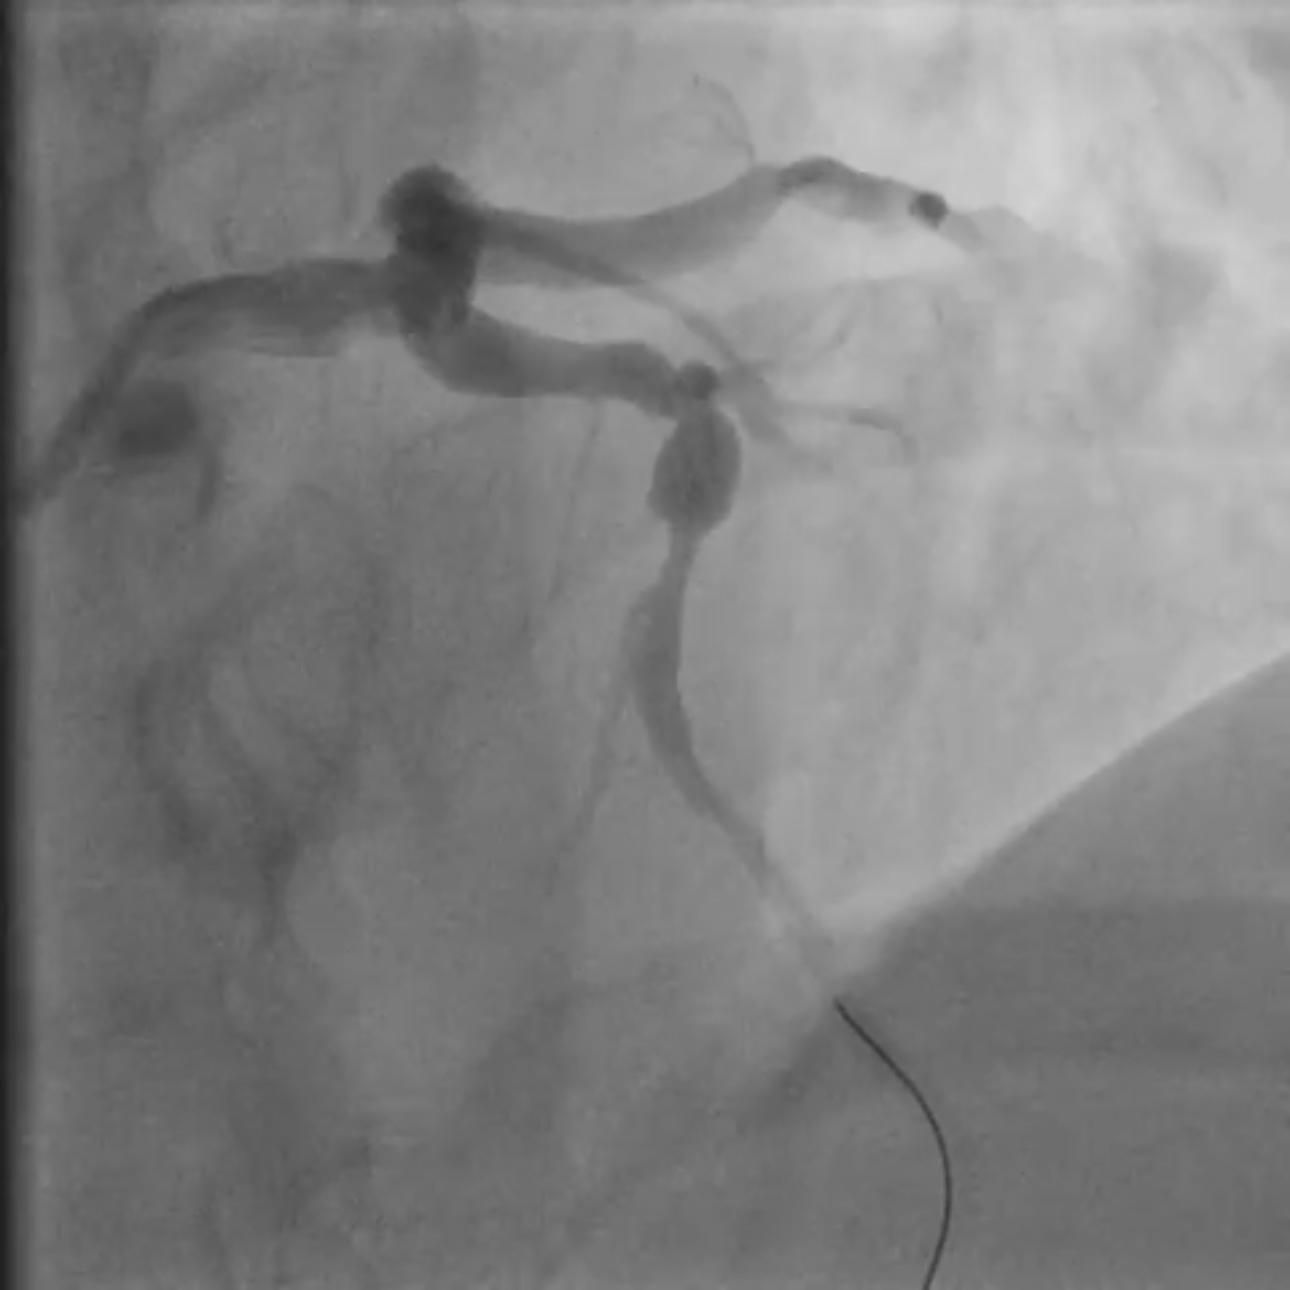

Coronary angiography revealed two severe stenoses in the mid left anterior descending (LAD) artery, separated by a short fusiform aneurysmal segment. The aneurysm was located between diseased segments and measured approximately 6 mm in diameter. A diagonal branch originated close to the proximal edge of the aneurysm. No thrombus or flow limitation was seen, and TIMI 3 flow was maintained pre-intervention.

Coronary angiography revealed two critical stenoses in the mid–left anterior descending (LAD) artery separated by a short fusiform aneurysmal segment. A diagonal branch originated near the proximal aneurysm margin. Implanting a covered stent was avoided due to the high risk of diagonal branch occlusion, and a drug-eluting balloon (DEB) strategy was rejected because it offered no vessel scaffolding and could destabilize the aneurysmal wall. A dual drug-eluting stent (DES) bridging technique was selected to stabilize the aneurysmal segment while maintaining branch perfusion. The procedure was performed via right radial access using a 6F XB guide catheter for enhanced support. A floppy guidewire was advanced into the distal LAD. Lesion preparation was performed with a 2.5 mm semi-compliant balloon. A 3.0 ¡¿ 15 mm DES was first deployed distally to treat the distal stenosis and establish a stable anchoring platform on healthy vessel. A second DES (3.5 ¡¿ 22 mm) was then implanted across the aneurysmal segment, with distal overlap onto the first stent to secure the construct outside the aneurysm. The proximal landing zone was carefully positioned in healthy vessel proximal to the aneurysm. Post-dilatation was deliberately limited to the landing zones with a non-compliant balloon to minimize mechanical stress on the aneurysmal wall. Final angiography showed optimal stent expansion, preserved flow to the diagonal branch, no dissection or perforation, and TIMI 3 flow. The patient received unfractionated heparin during PCI and dual antiplatelet therapy (aspirin + ticagrelor) per ACS guidelines.